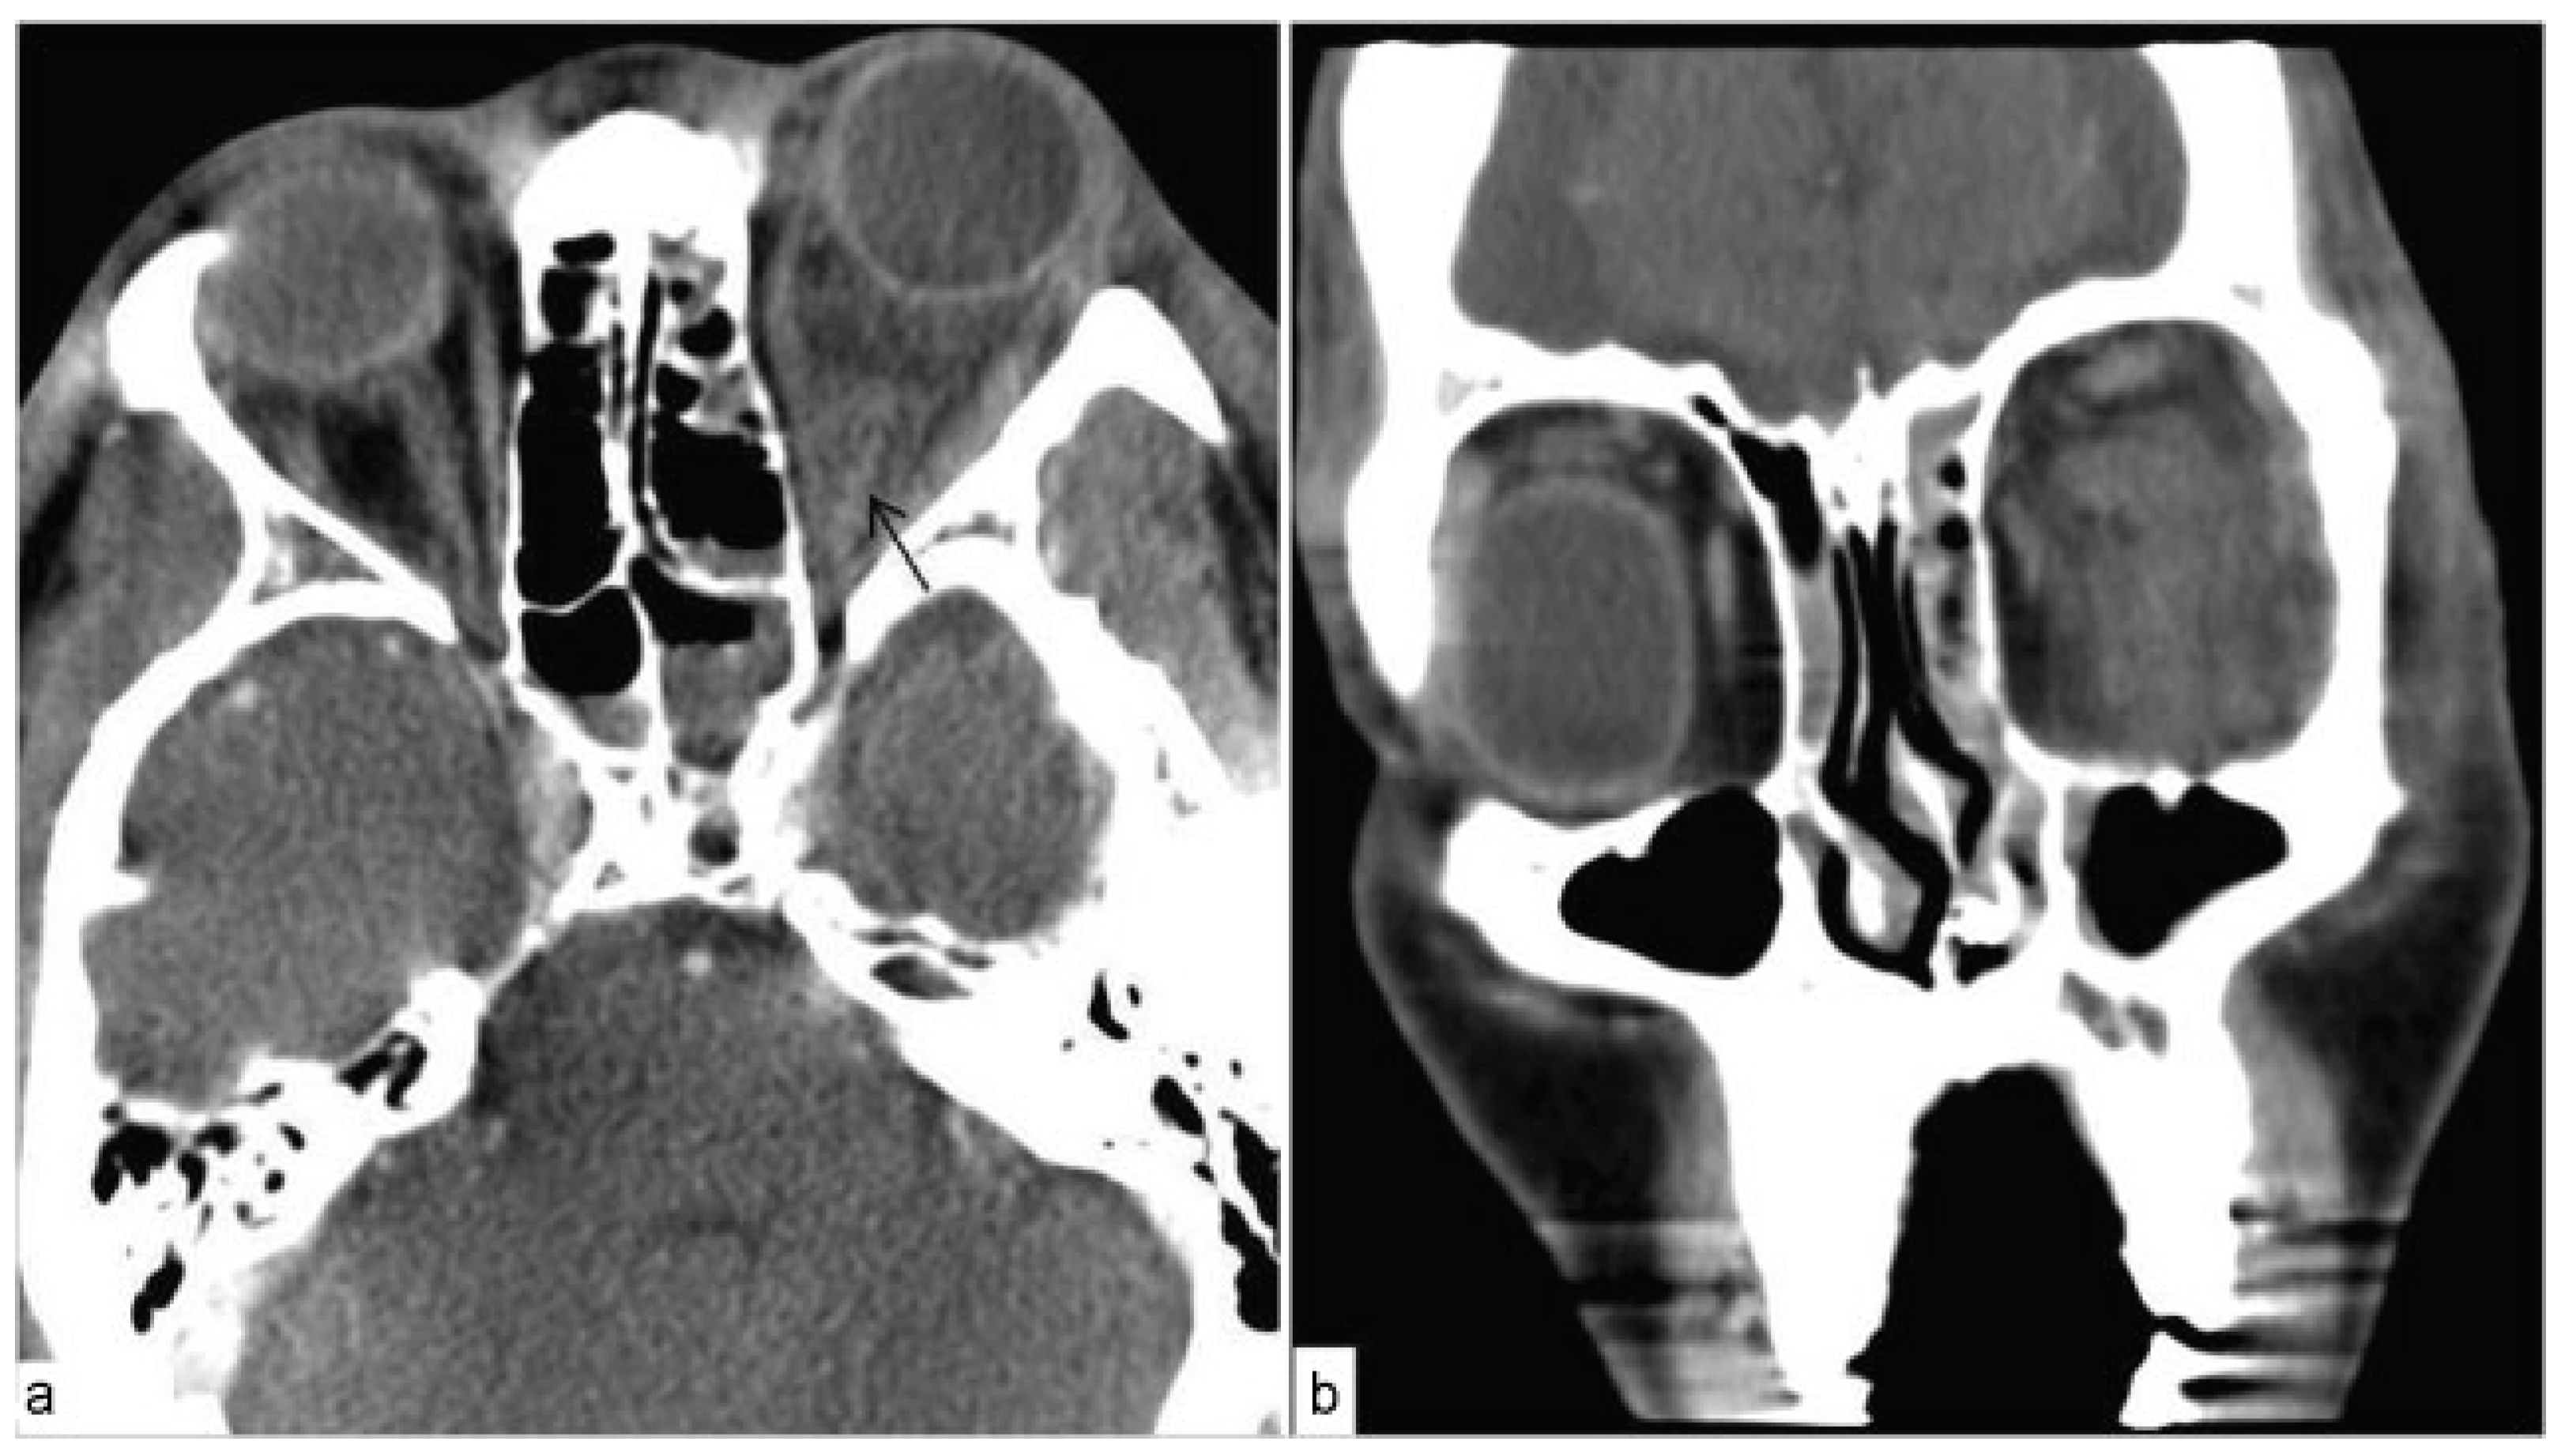

Out of 80 patients over the 9.5 year period, we had 1 (1.3%) immediate postoperative complication. Twenty hours postoperatively from an isolated orbital floor fracture, proptosis and firmness of the globe occurred in the operative eye. The patient was intubated and sedated on the ventilator due to other injuries. Intraocular pressure (IOP) of the affected eye was measured at 32 mm Hg. A lateral canthotomy and cantholysis were performed at the bedside; however, IOP continued to rise up to 52 mm Hg over the subsequent 2 hours. Computed tomography (CT) examination confirmed RBH (Figure 1) and the patient was taken to the operating room for emergent orbital exploration. Inferior orbital bleeding was controlled with bipolar cautery, the implant was removed, and a maxillary antrostomy was performed to allow drainage. IOPs declined to 22 mm Hg 2 hours postoperatively and the patient eventually awoke and healed without sequelae.

Figure 1. CT ~24 hours post-op from orbital floor repair confirming retrobulbar hematoma. (a) Axial image highlights proptosis with increase hyperdensity within the left posterior orbit (arrow). (b) Coronal images show increase hyperdensity within the left orbit with distortion of the softtissue planes.